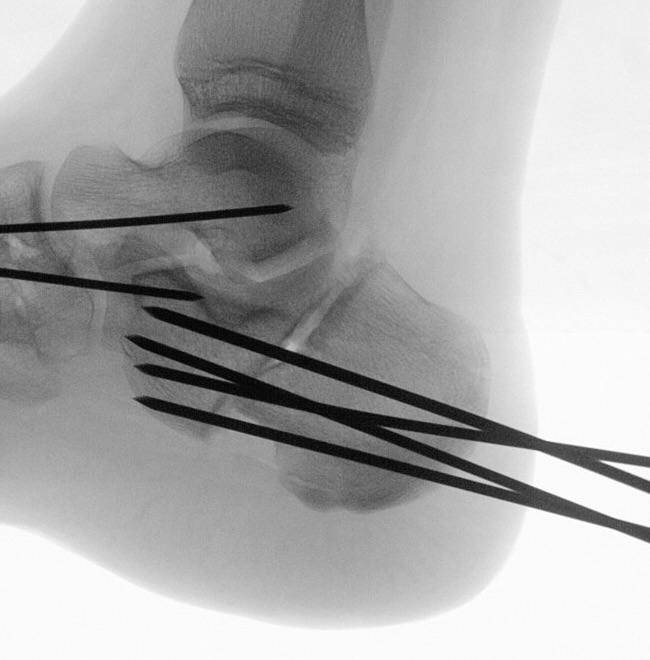

Calcaneus-Osteotomie

Die minimalinvasive Calcaneusverschiebeosteotomie bietet eindeutige Vorteile gegenüber dem offenen Verfahren, sodass wir bei Kindern und Jugendlichen nahezu keine offene Verschiebeosteotomie mehr durchführen. Am Calcaneus liegt die offene Wachstumsfuge dorsal. Bei der Durchführung müssen Schenkel der V-förmigen Osteotomie daher etwas steiler angelegt werden, in einem stumpfen Winkel (siehe Abb. 3 a-j). Für die Osteotomie liegen unsere Patienten auf dem Rücken und der BV wird für die exakte Seitaufnahme eingestellt. Der Fuß lagert auf einem hohen OP-Kissen und die Osteotomie kann bequem mit einem langen Kirschner-Draht und einem sterilen Stift angezeichnet werden (Abb. 15).

Abb. 15 a-b: Lagerung für die Calcaneus-Osteotomie minimalinvasiv.

Zum Lesen der Bildbeschreibung und zur Vollansicht bitte die Bilder anklicken. Bilder: A. Helmers.

Damit lässt sich im Verlauf Röntgenstrahlung für die jungen Patienten vermeiden und die minimalinvasive Osteotomie kann sicher durchgeführt werden. Anschließend erfolgt die Verschiebung oder Impaktion. Ist ein Gleiten nach plantar oder cranial des distalen Fragmentes erwünscht, wird die Osteotomie schräg ohne V-Form entweder verlängernd oder verkürzend durchgeführt (Abb. 16).

Durch den knöchernen Defekt der Fräse gelingt die Verschiebung bei der minimalinvasiven Osteotomie im Fall von strukturell festen Klumpfüßen mit starkem Zug der verkürzten Achillessehne oder bei einer fixierenden spastischen Grunderkrankung einfacher gegenüber dem offen Verfahren. Ein weiteres Plus bei hyperaktiven Weichteilen ist die Vermeidung der ungewollten Cranialisierung des dorsalen Fragmentes durch die V-förmige Osteotomie (Abb. 16).